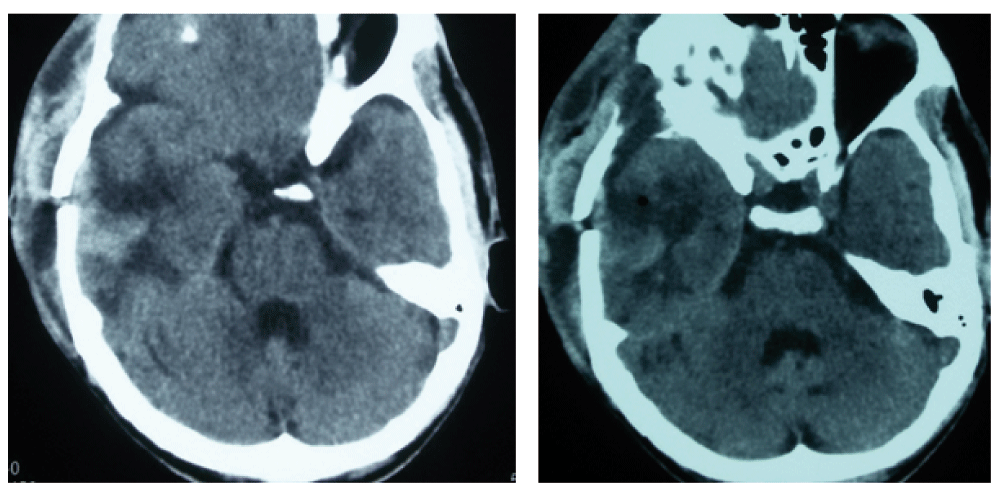

A 50-year-old male from Siraha, a distant village in Nepal, was referred to our neurosurgical centre following a road traffic accident after being hit by a speeding car. The patient had a brief loss of consciousness and a single episode of vomiting following the incident. There was no history of seizurogenic activity observed during the transfer. On arrival to the emergency department, his Glasgow coma scale (GCS) was E3M6V5 with no paucity in movement of any limbs. His vital parameters were within normal range with blood pressure of 130/90, pulse rate of 86/min and oxygen saturation of 99% in room air. It was difficult to assess differences in pupillary size as he had corneal opacity on the left eye, resulting from an injury sustained during his childhood. However, on close examination, we observed that there was prominence of the forehead wrinkles on the right half of his face especially when the patient was trying to open his eyes during conversation, which we termed as frontalis sign (Figure 1). The wrinkles on the contra lateral half were normal with no abnormal deviation of angle of the mouth dismissing the differential diagnosis of upper facial nerve palsy. Because of the finding, we suspected impending uncal herniation in the patient and thereby advised for an emergency computed tomography (CT) scan of the head. It revealed right sided huge temporo-parietal contusion with thin fronto-temporo-parietal subdural hematoma with features of uncal herniation (Figure 2). The condition was explained to his relatives and they were counseled for emergency evacuation of the hematoma. On their consent, we performed a craniotomy, evacuation of the subdural hematoma and removal of the contusion. Following the procedure, the brain was lax and pulsatile. The patient was extubated without any untoward events in the postoperative period. The frontalis sign diminished following the surgery (Figure 3). The post operative scan confirmed resolution of the mass effect and normalization of the cisternal anatomy (Figure 4). The patient was started on Levtiracetam 500 mg intravenously every 12 hours which was changed to oral medication after three days as seizure prophylaxis. The patient was discharged after suture removal on the 8th postoperative day. The patient followed up in the outpatient clinic 2 weeks later in sound health. Eye opening was near normal. The patient was advised for monthly follow up.